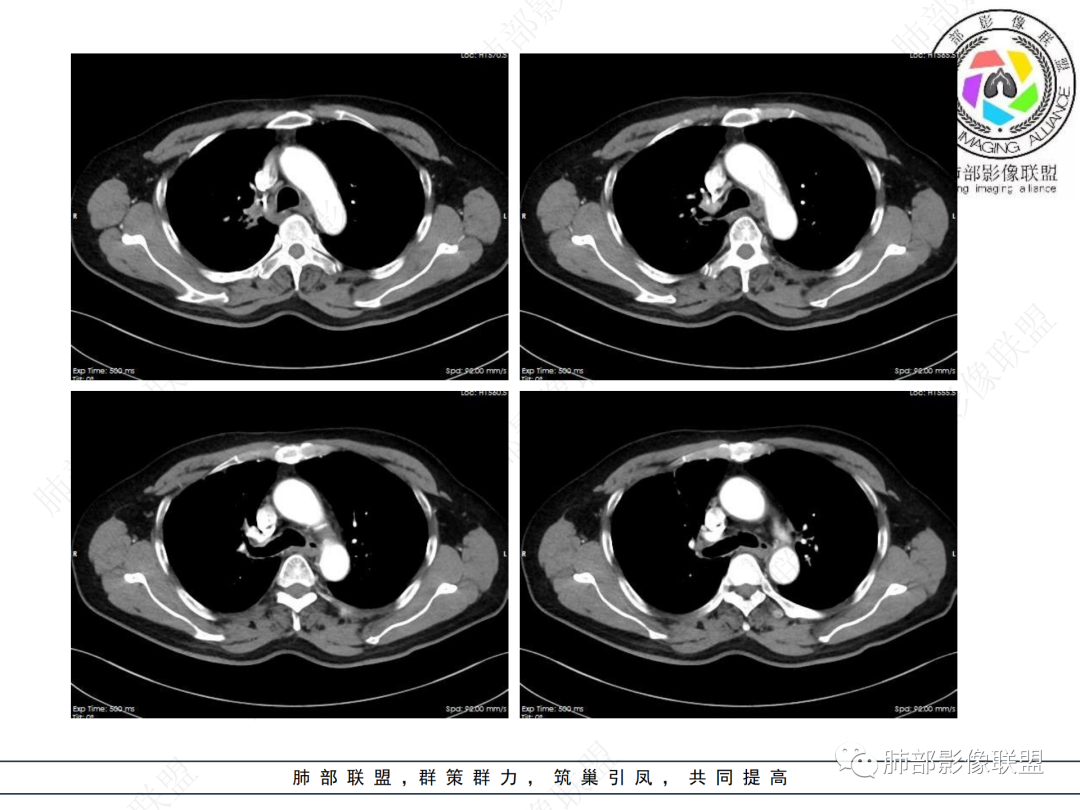

主要在慢性炎性病变与腺癌之间鉴别,病灶有膨胀性生长,支气管未见阻塞,支气管僵硬,增强病灶内可见强化,支气管内部壁增厚,偏向占位性病变,腺癌可能。

右肺上叶可见一团块影,边界清,有膨隆有凹陷,边缘可见毛刺,斜裂可见牵拉,不均匀强化,内可见液化,临近支气管未见明确阻塞,考虑腺癌可能,鉴别脓肿,结核等

病史2年。右肺上叶团片影,边缘部分清晰,平直,相邻纵隔侧胸膜黏连较广泛,周围见斑点。增强均匀强化。首选炎性肉芽肿性病变(慢性炎症,结核)。肿瘤性病变待排。食道上段形态异常建议相关检查。

右肺上叶团块,边缘毛糙,长索条,周围斑点影,邻近胸膜增厚,不均匀强化,其内小低密度灶边界清,考虑炎性肉芽肿,腺癌待排

老年男性,咳嗽2年,右上肺类圆形新生物,毛刺,不均匀强化,考虑肺癌,支气管截断不明显,腺癌?

右上胸廓缩小,叶间裂移位,尖段软组织影,前段支气管壁增厚,双上肺多发结节及条片影,增强后尖段软组织影内见多发低密度影,呈环状强化,考虑慢性肉芽肿,腺癌待排

男性,69岁 反复咳嗽2年余,加重3天入院。CT示右肺上叶尖段不规则实变影,周边伴条索影,支气管未见明显堵塞,增强不均匀强化,考虑为恶性,腺癌可能

老年男性,慢性病程,右肺上叶团块影,边界清晰,边缘毛刺,脐凹征,胸膜牵拉,不均匀强化,支气管壁增厚,考虑恶性,腺癌可能,鉴别肉芽肿、结核

男,69,反复咳嗽2年,加重3天入院,右肺上叶软组织密度肿块影,边界尚清晰,边缘见毛刺及胸膜牵拉,右肺上叶支气管壁增厚,增强扫描不均匀性强化,考虑腺癌可能,鉴别炎性病变。

老年男性,右肺上叶体积小,见高密度团块,边缘模糊,并见多发长索条,增强后不均匀强化,考虑炎性肉芽肿性病变,鉴别腺癌

病程长,右肺上叶团片影,边缘毛糙,部分膨隆,长索条,周围长条索及结节,邻近胸膜增厚,不均匀强化,首先考虑炎性肉芽肿,鉴别腺癌

右肺上叶团块周围多发斑索,不均匀强化,支气管无明显堵塞,咳嗽两年,首先考虑慢性炎性病变,肺结核可能,鉴别腺癌

右肺上叶见不规则团块,边缘清晰,周围可见长索条及斑片影,胸膜顶增厚,右侧斜裂部分增厚,右上肺体积略缩小,增强后不均匀强化,考虑炎性肉芽肿性病变,结核?鉴别腺癌

右肺上叶体积变小,见不规则实性病灶,边缘有平直,长软毛刺,邻近胸膜明显增厚,叶间胸膜牵拉上提、局部凹陷;病灶周围不干净,可见长索条影;近端支气管壁略增厚。增强后增强不均匀,有低密度坏死,间隔较厚。考虑慢性炎性肉芽肿,结核可能,鉴别腺癌。

右侧胸廓变小,右肺上叶团块,边缘毛糙,长索条,周围斑点影,邻近胸膜增厚,气管不规整,密度不均,不均匀强化,考虑炎性肉芽肿,腺癌待排。

右肺上叶尖后段不规则斑块病灶,后缘以斜裂为界,有边缘平直,周围见纤维及多发小卫星灶,邻近胸膜反应性增厚,纵隔胸膜下少量积液,同时右肺中叶内侧段支气管扭曲及牵引性扩张,周边见爬行征,胸廊入口变窄,纵隔未见淋巴结肿大,综合上述慢性炎性肉芽肿,结核可能性大,支气管镜肺泡灌洗!

结合本病例,老年男性患者,慢性病程,急性加重,无吸烟史,影像学表现为右肺上叶尖后段斑片实变密度影,整体边界清晰,边缘平直收缩为主,周边散在纤维条索影,内部见支气管内粘液栓,血管影走形正常,没有明显破坏,增强扫描明显强化,缺乏典型分叶毛刺、胸膜改变,病灶也未显示清楚的磨玻璃勾边,病灶大而肺门纵隔未见肿大淋巴结,综合考虑慢性炎性肉芽肿可能性大。但恶性,结核能完全排除吗?我想对临床医生来说还是有很大考验的。